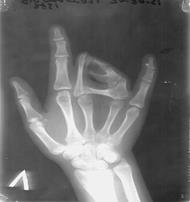

Сложное сращение возникает, когда сращенные пальцы имеют самостоятельные дефекты развития.

Рис. 7. Сложная форма синдактилии